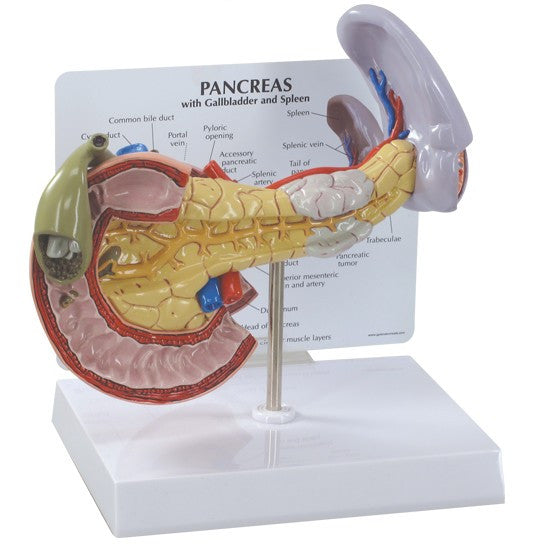

Enhance medical education with our collection of digestive system anatomical models including the stomach, liver, gallbladder, pancreas & colon models. Discover the anatomy of healthy organs as well as common gastrointestinal diseases such as stomach ulcers, gallstones and liver cirrhosis. Our digestive system anatomy posters are ideal for study and patient education.

At AnatomyStuff we stock a diverse range of digestive system anatomical models to suit your training needs. From budget models and affordable medical education posters to highly advanced 3D printed bowel models, you can transform medical training and patient education. As well as our own exclusive collection, we are proud resellers of 3B Scientific, Anatomy Lab, Denoyer-Geppert Science Company, ESP Models, Erler Zimmer and GPI Anatomicals. Explore our exclusive collection of digestive system anatomy charts, posters, fine art prints and digital anatomy study guides. Discover the anatomy of key organs like the liver, stomach, pancreas and bowel as well as the pathophysiology of common conditions like peptic ulcer disease, coeliac disease, IBD and much more. We have anatomy posters suitable for school children all the way up to medical degree level. From a liver anatomy poster to a digital study guide all about common GI disorders, find exactly what you need right here to enhance medical training and patient education.